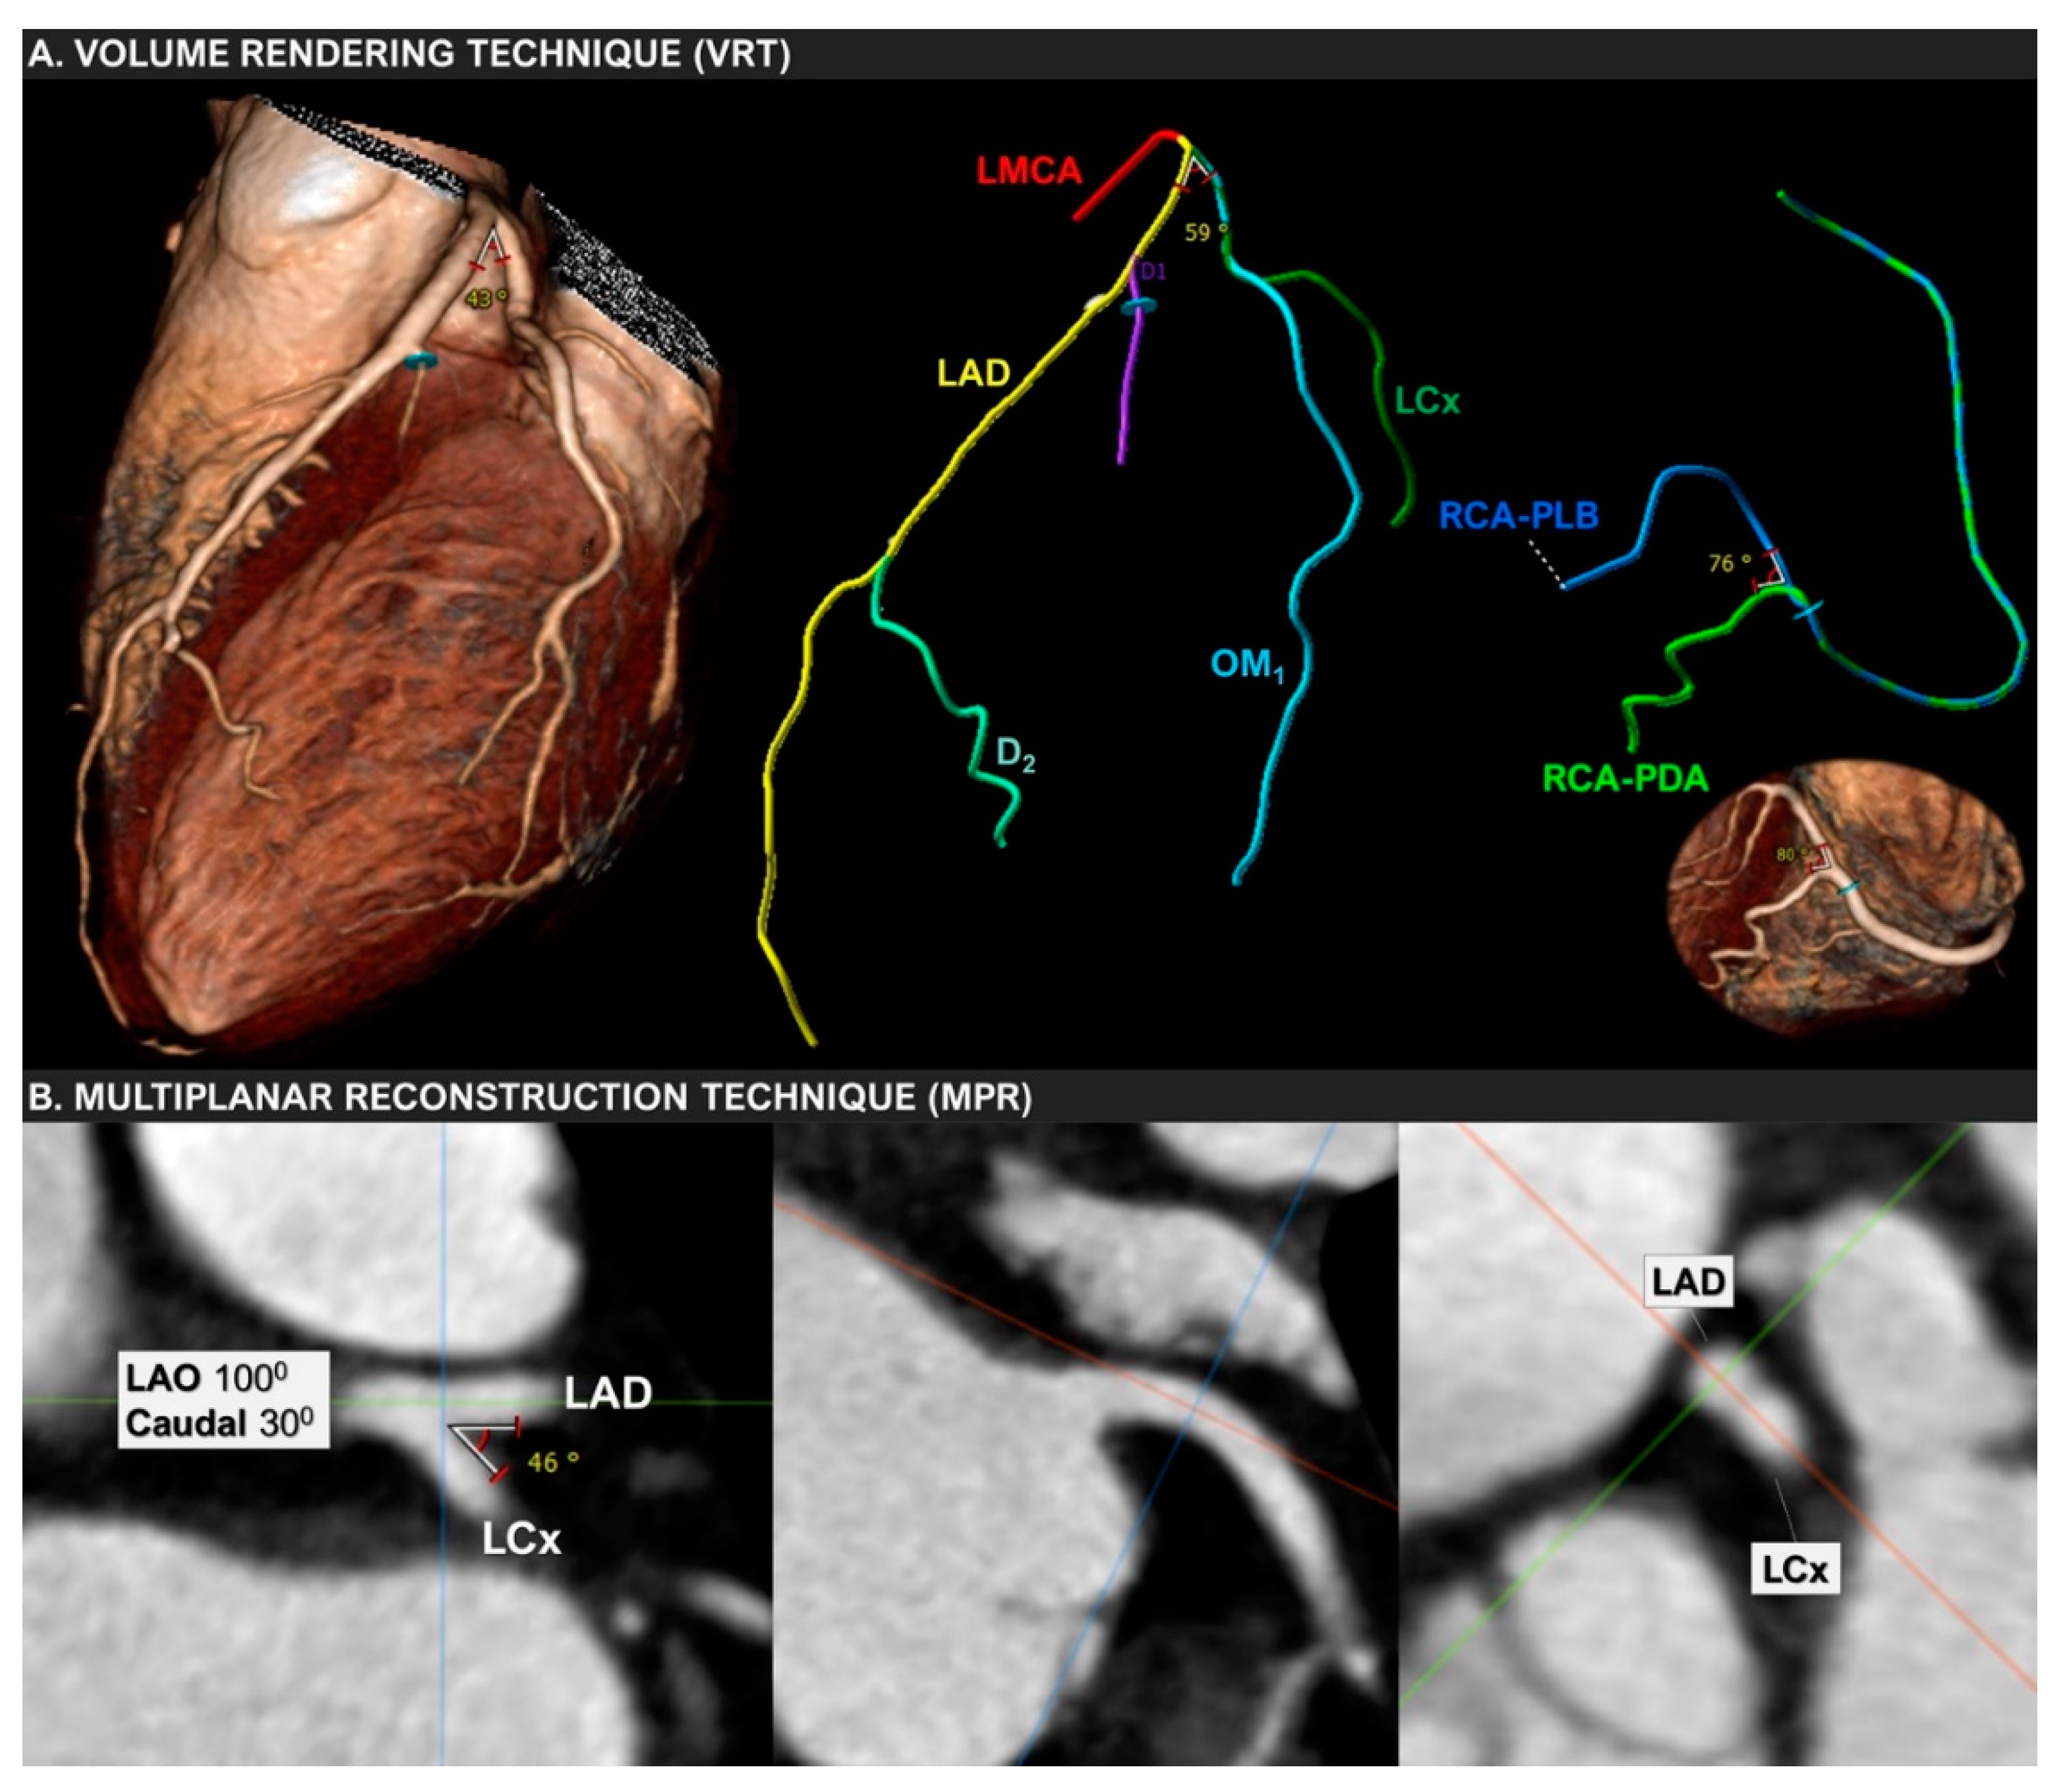

Finally, the ongoing GEOMETRY-CTA study [40] aims to introduce a quantitative, non-invasive imaging biomarker utilizing coronary artery geometric features, clinical and genetic risk factors, serum biomarkers, epicardial fat volume, and the coronary artery calcium score (CACS), to predict the presence and the complexity of CAD on CCTA and investigate its prognostic value regarding adverse cardiovascular events (Figure 2). The study intends to recruit 100 consecutive patients with suspected CAD and low/intermediate pre-test probability. Coronary geometrical characteristics such as the angulation of coronary bifurcations, tortuosity, CAVi [38], and vessel-length will be assessed with multi-planar reformation and volume rendering techniques (Figure 3) and integrated into a single geometric risk score. The extent and vulnerability of plaque burden will be calculated using several anatomical scoring systems such as the Leiden CTA risk score [41] and CT-adapted Gensini score [42]. Patients will be prospectively followed for 12 months after enrollment. In clinical practice, the utilization of such an approach could improve risk stratification and help guide downstream personalized management. Furthermore, the derived index will be available for incorporation in larger national prospective studies for further cardiovascular risk stratification.

Figure 3. Volume-rendering (VRT) and multiplanar reconstruction (MPR) techniques used to measure the bifurcation angle between LAD and LCx in a 67-year-old woman with mild non-obstructive coronary artery disease.